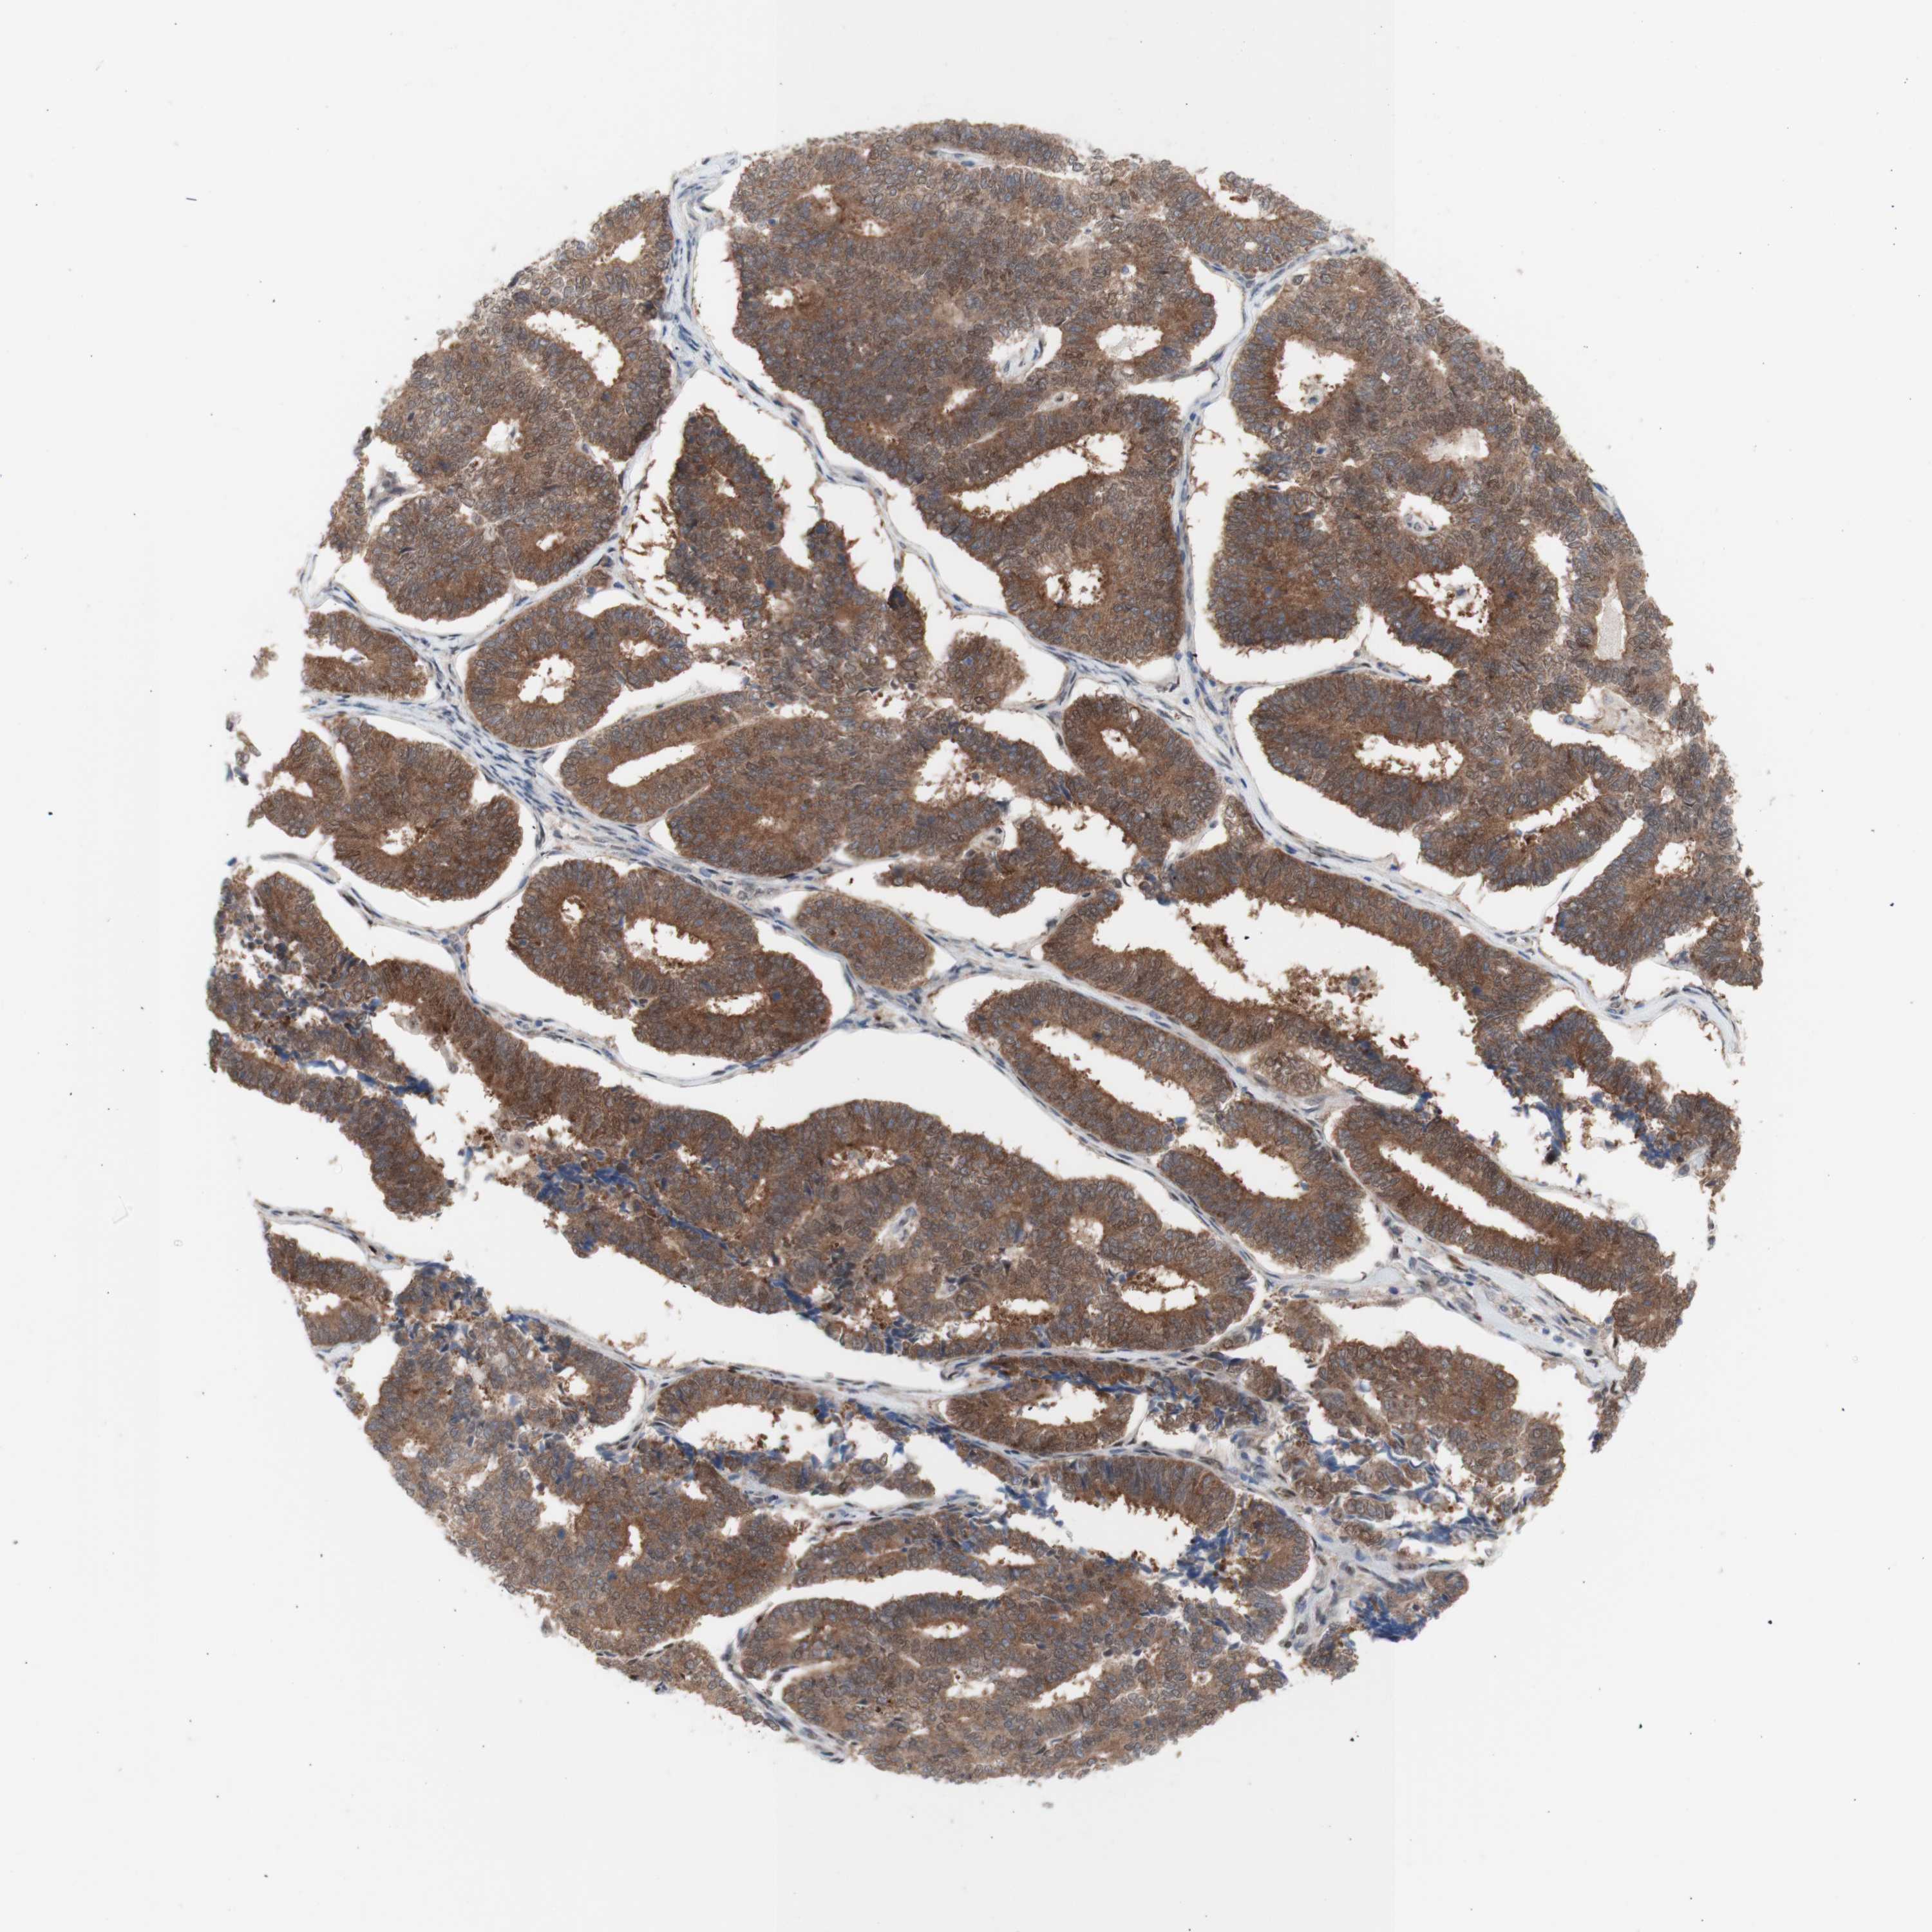

ENDOMETRIAL CANCER - Protein expressioni

A mouse-over function shows sample information and annotation data. Click on an image to view it in a full screen mode. Samples can be filtered based on level of antibody staining by selecting one or several of the following categories: high, medium, low and not detected. The assay and annotation is described here.

Note that samples used for immunohistochemistry by the Human Protein Atlas do not correspond to samples in the TCGA dataset.

Antibody stainingi

Antibody staining in the annotated cell types in the current human tissue is reported as not detected, low, medium, or high, based on conventional immunohistochemistry profiling in selected tissues. This score is based on the combination of the staining intensity and fraction of stained cells.

Each image is clickable and will lead to virtual microscopy that enables deeper exploration of all samples and also displays staining intensity scores, fraction scores and subcellular localization as well as patient and tissue information for each sample.

Antibody HPA005525

Antibody HPA064708

Antibody CAB012459

Staining

High

Medium

Low

Not detected

Intensity

Strong

Moderate

Weak

Negative

Quantity

>75%

75%-25%

<25%

None

Location

Nuclear

Cytoplasmic/membranous

Cytoplasmic/membranous,nuclear